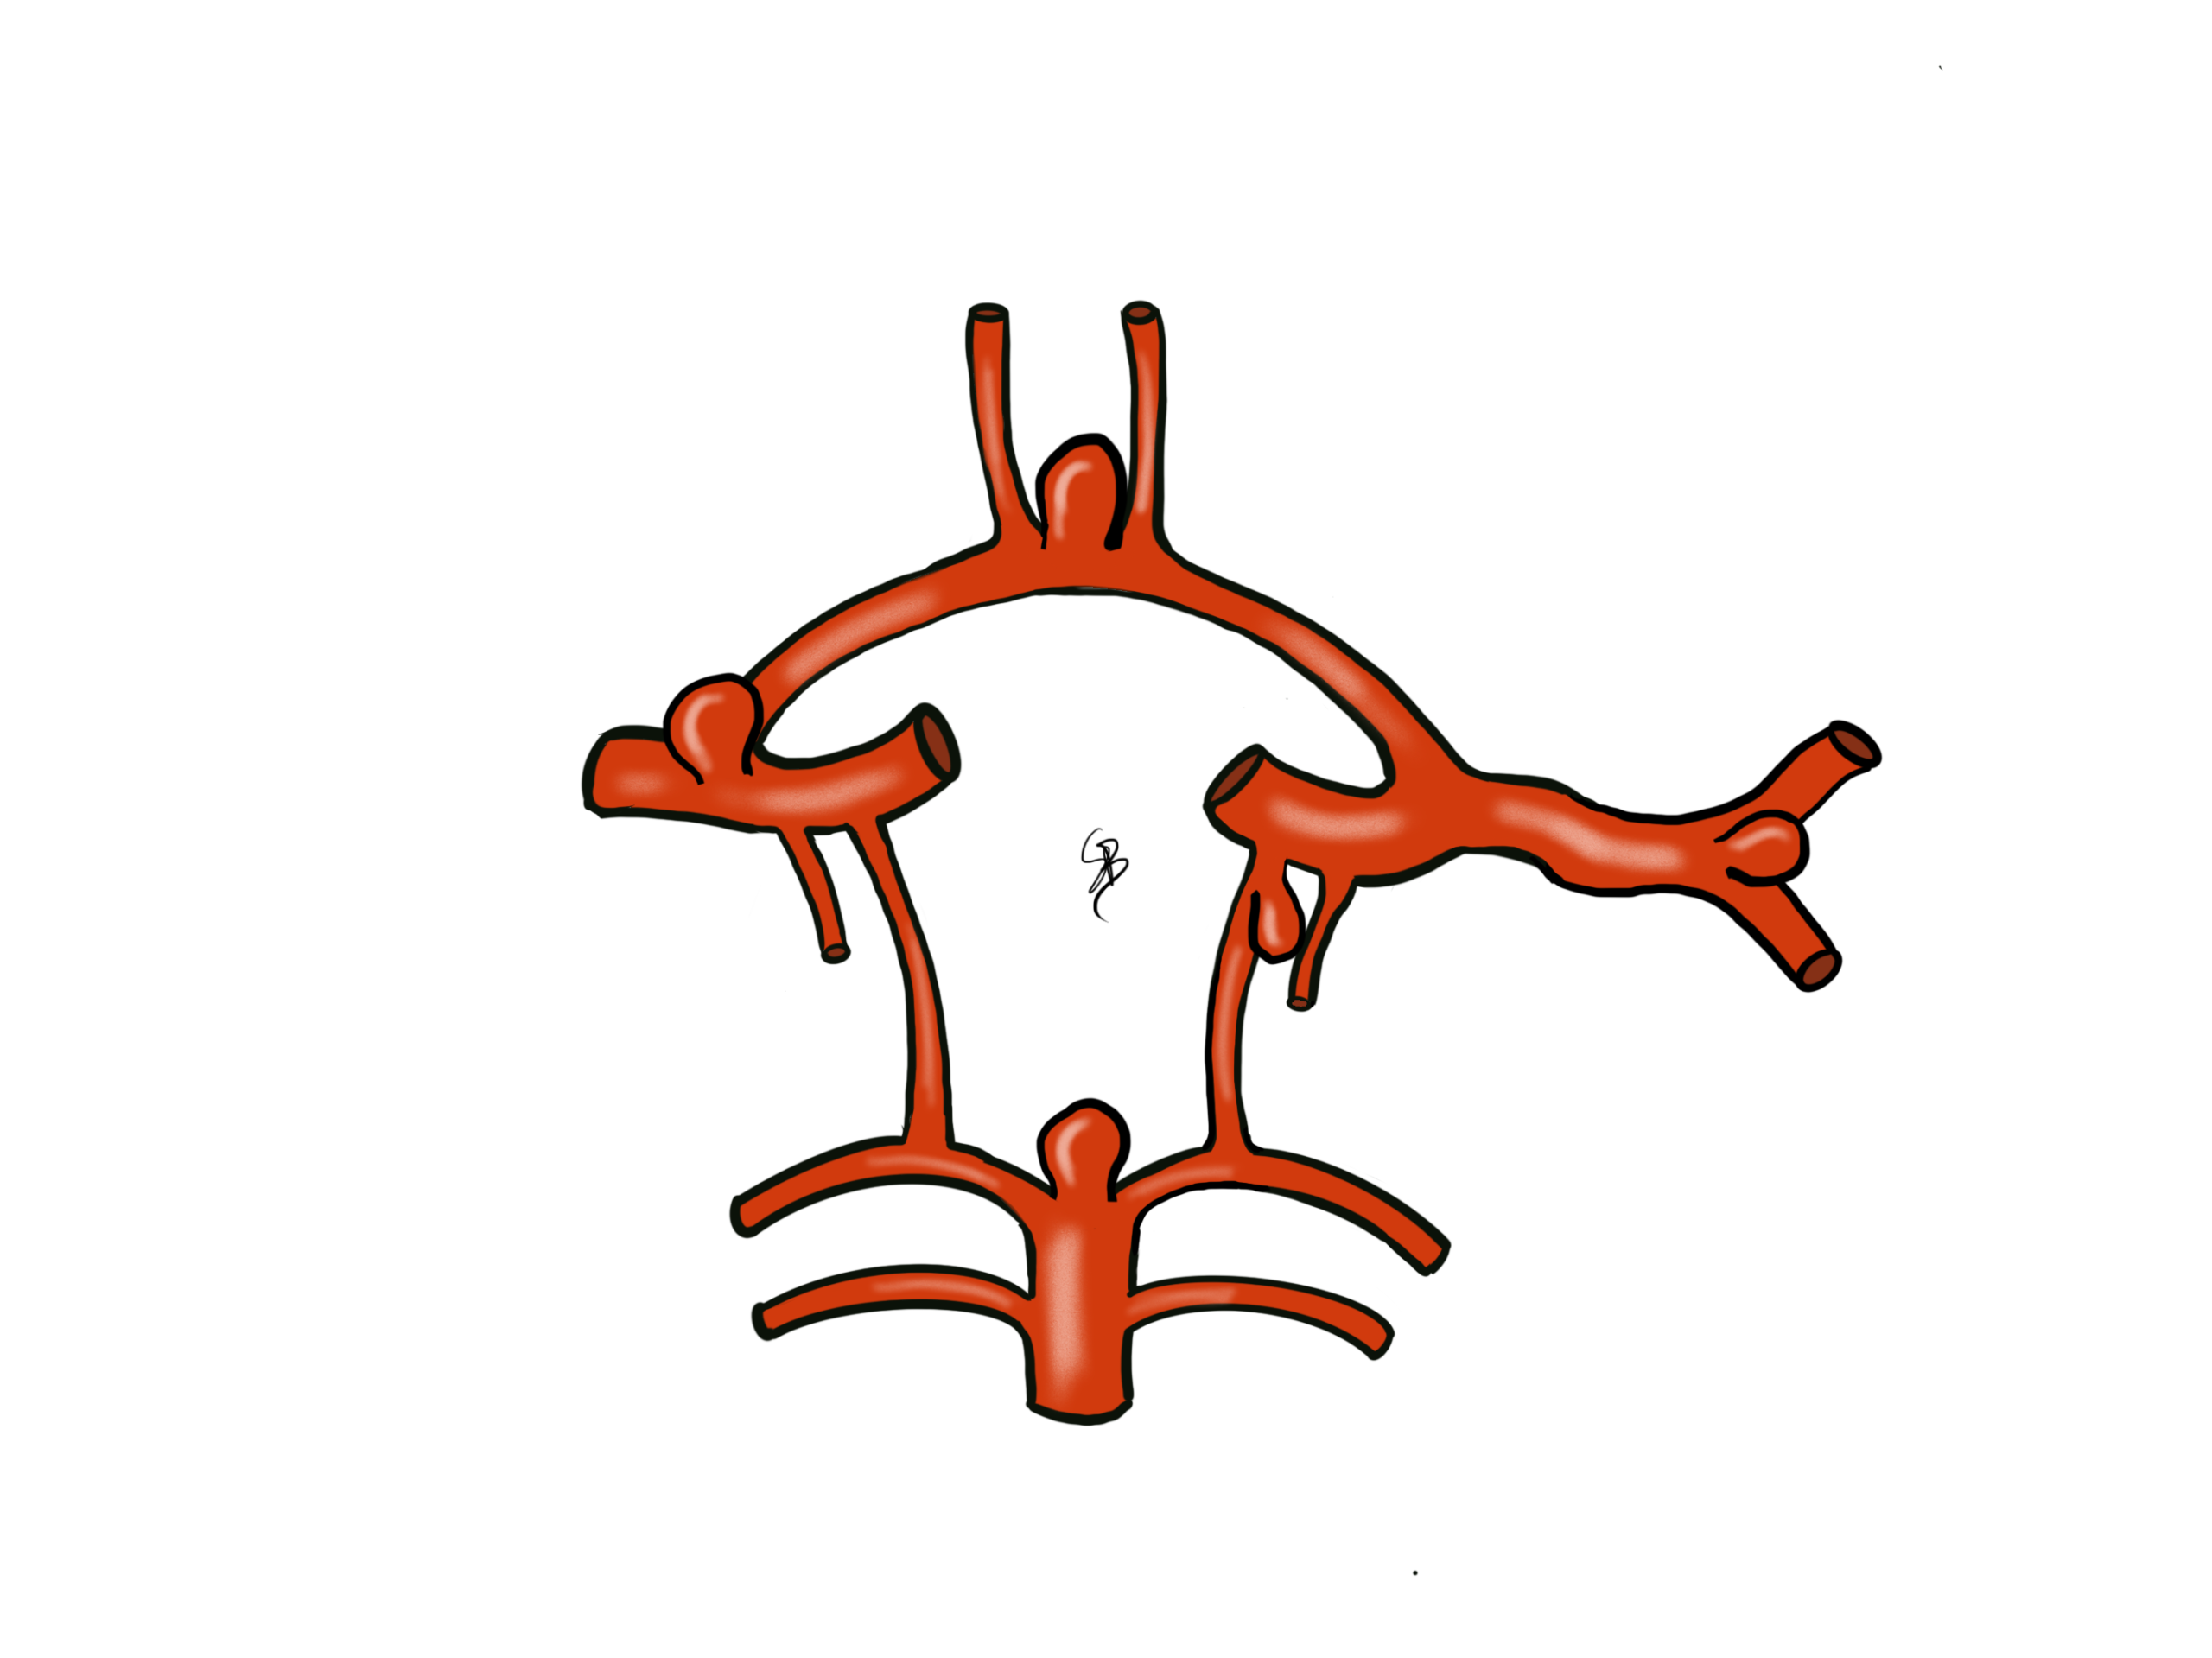

Multipli aneurismi su arterie cerebrali

L’aneurisma cerebrale è dovuto alla degenerazione della parete di un’arteria cerebrale. La sua formazione è un processo lento, favorito da fattori di rischio cardio-vascolari comuni (fumo, ipertensione arteriosa, colesterolo, diabete) ai quali si aggiungono alcuni fattori di rischio genetici. Un aneurisma cerebrale è molto raramente responsabile di un deficit neurologico se non è rotto. In rari casi di aneurismi di dimensione importante, l’aneurisma può provocare una compressione delle strutture neurologiche, come ad esempio un nervo cranico.

La scoperta occasionale di un aneurisma cerebrale è frequente e un parere specialistico neurochirurgico è assolutamente necessario. Secondo dei criteri precisi, si deve stabilire se l’aneurisma presenta un rischio elevato di rottura e, di conseguenza, di provocare un’emorragia cerebrale. In questo caso è possibile proporre un trattamento «preventivo» dell’aneurisma. I fattori di rischio che aumentano la probabilità di rottura dell’aneurisma sono le dimensioni della sacca sopra 7mm, la sua localizzazione su alcune arterie cerebrali, il fumo, la pressione arteriosa alta ed il numero di aneurismi presenti.